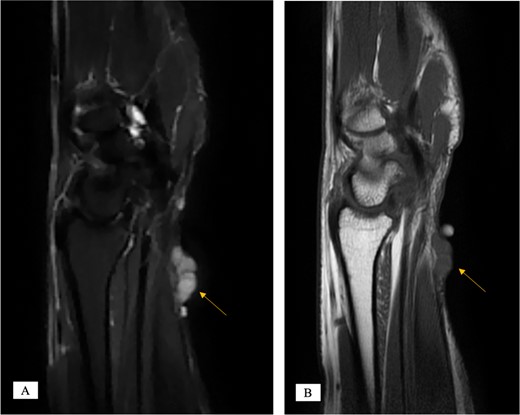

X-ray showed a well-defined non-aggressive lytic bony lesion of the first metacarpal bone (Fig. 1). Magnetic resonance imaging (MRI) showed a grossly stable skin and subcutaneous multilobulated soft tissue mass located at the palmar aspect of the wrist joint measuring 6 × 2 × 3.3 cm3 in its maximum anteroposterior, transverse and craniocaudal dimensions, respectively (Figs 2 and 3). The lesion showed low and high signals in T1 - and T2-weighted images with homogenous contrast enhancement. The lesion was inseparable from the flexor carpi radialis and palmaris longus tendons without definite invasion or encasement. The lesion was not in continuity, however, with the serpiginous lytic bony lesion noted at the first metacarpal bone exhibiting low T1 and high T2 signals with peripheral enhancement and no cortical destruction or associated soft tissue component (Fig. 4).

MRI of the left distal forearm showing cutaneous and subcutaneous lobulated mass at the volar aspect of high T2 and low T1 signals with diffuse enhancement. (A) Sagittal T2-weighted fat saturated image. (B) Sagittal T1-weighted image.

MRI coronal T2-weighted fat saturated image showing intraosseous lesion of high T2 signal in the first metacarpal bone.